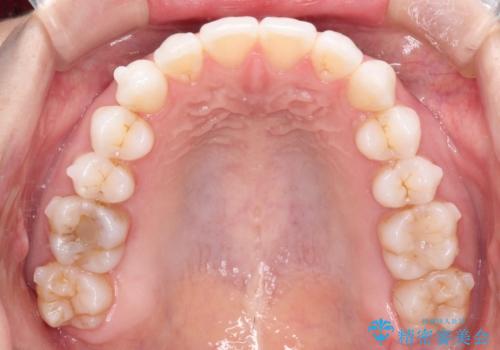

- インビザライン

- 1年6ヶ月

- 10-30回

- 主訴:「右上犬歯を引っ込めて、歯並びをキレイにしたい」

右上の八重歯を気にされてご来院されました。結婚式を控えていたため挙式にまでに可能な限りキレイにしたいとのことでした。

また、ホワイトニングも一緒にご希望されたため、挙式のタイミングに合わせてレーザーホワイトニングを施術させていただきました。